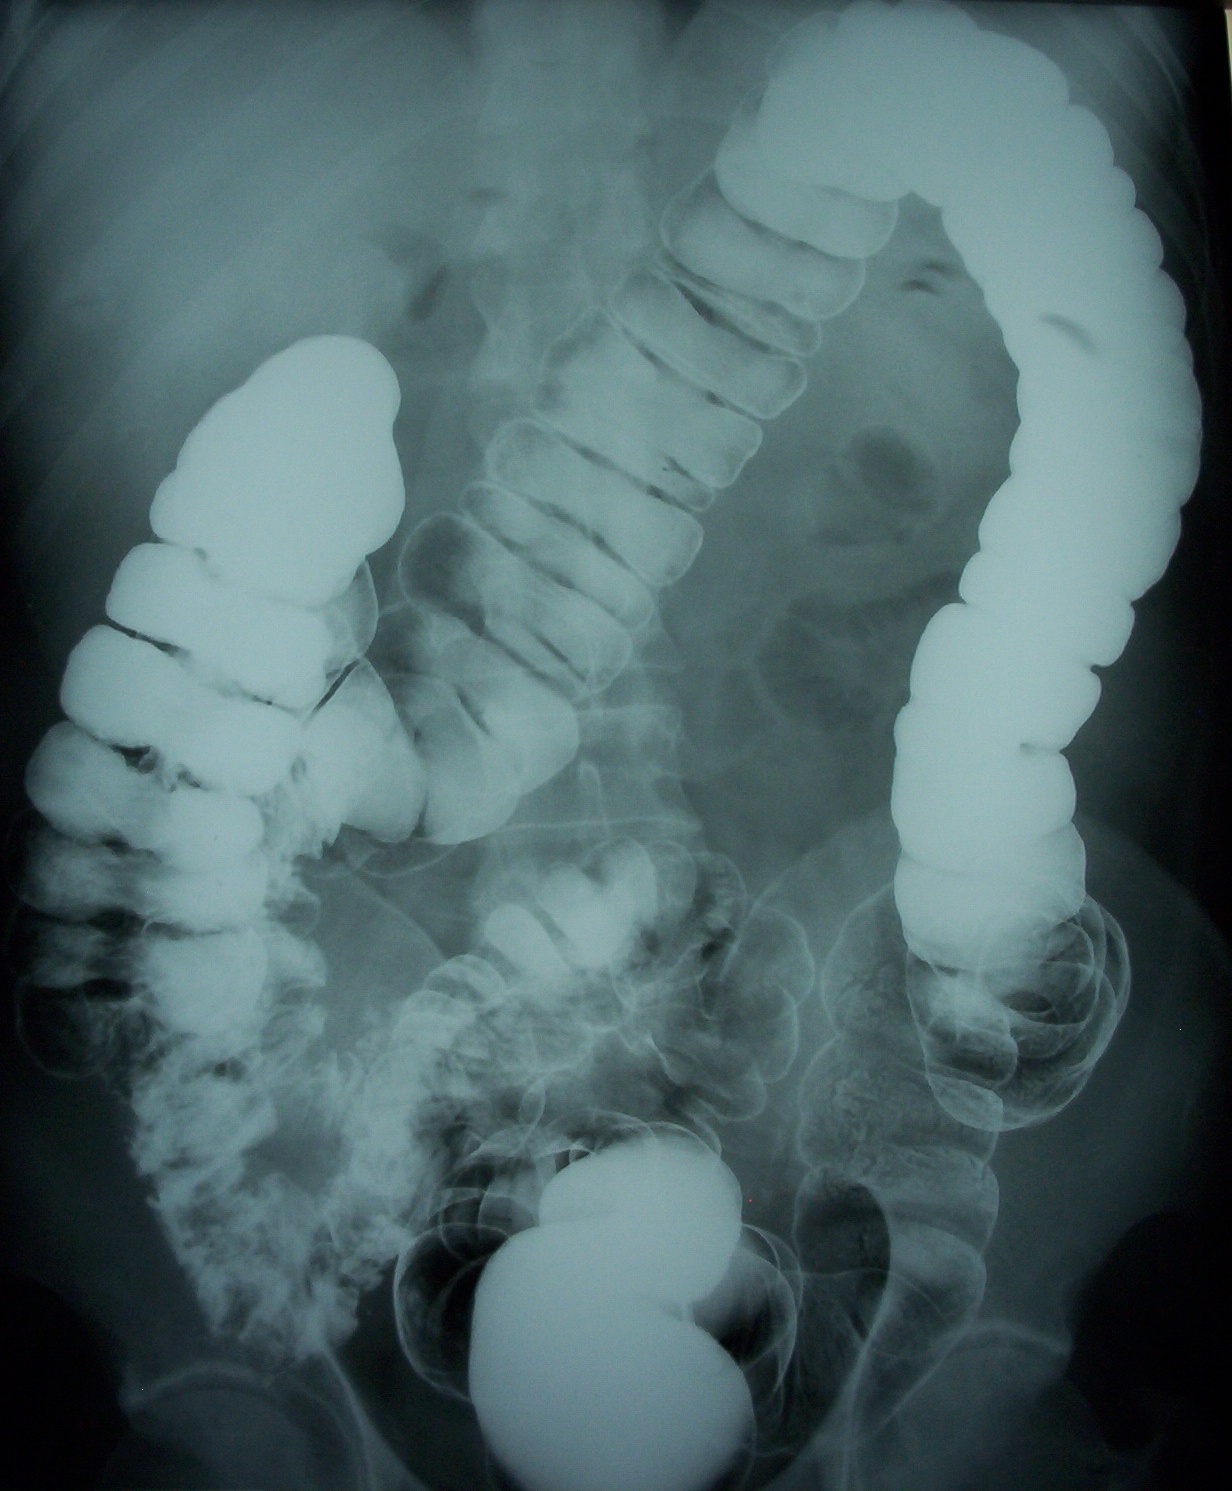

Feto cara cara2 Feto Oreja manos carita bebe Barret Barrett1 Pólipo Diverticulos Cancer rectal Transverso Duodeno Rayos%20x.jpg